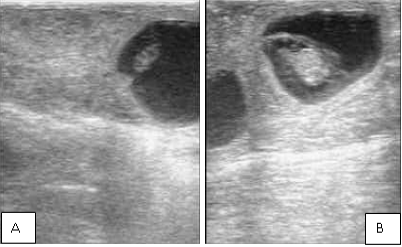

Figure 1

Ultrasound image of 30 days (A) and 45 days (B) pregnancy in Karan Fries cows.